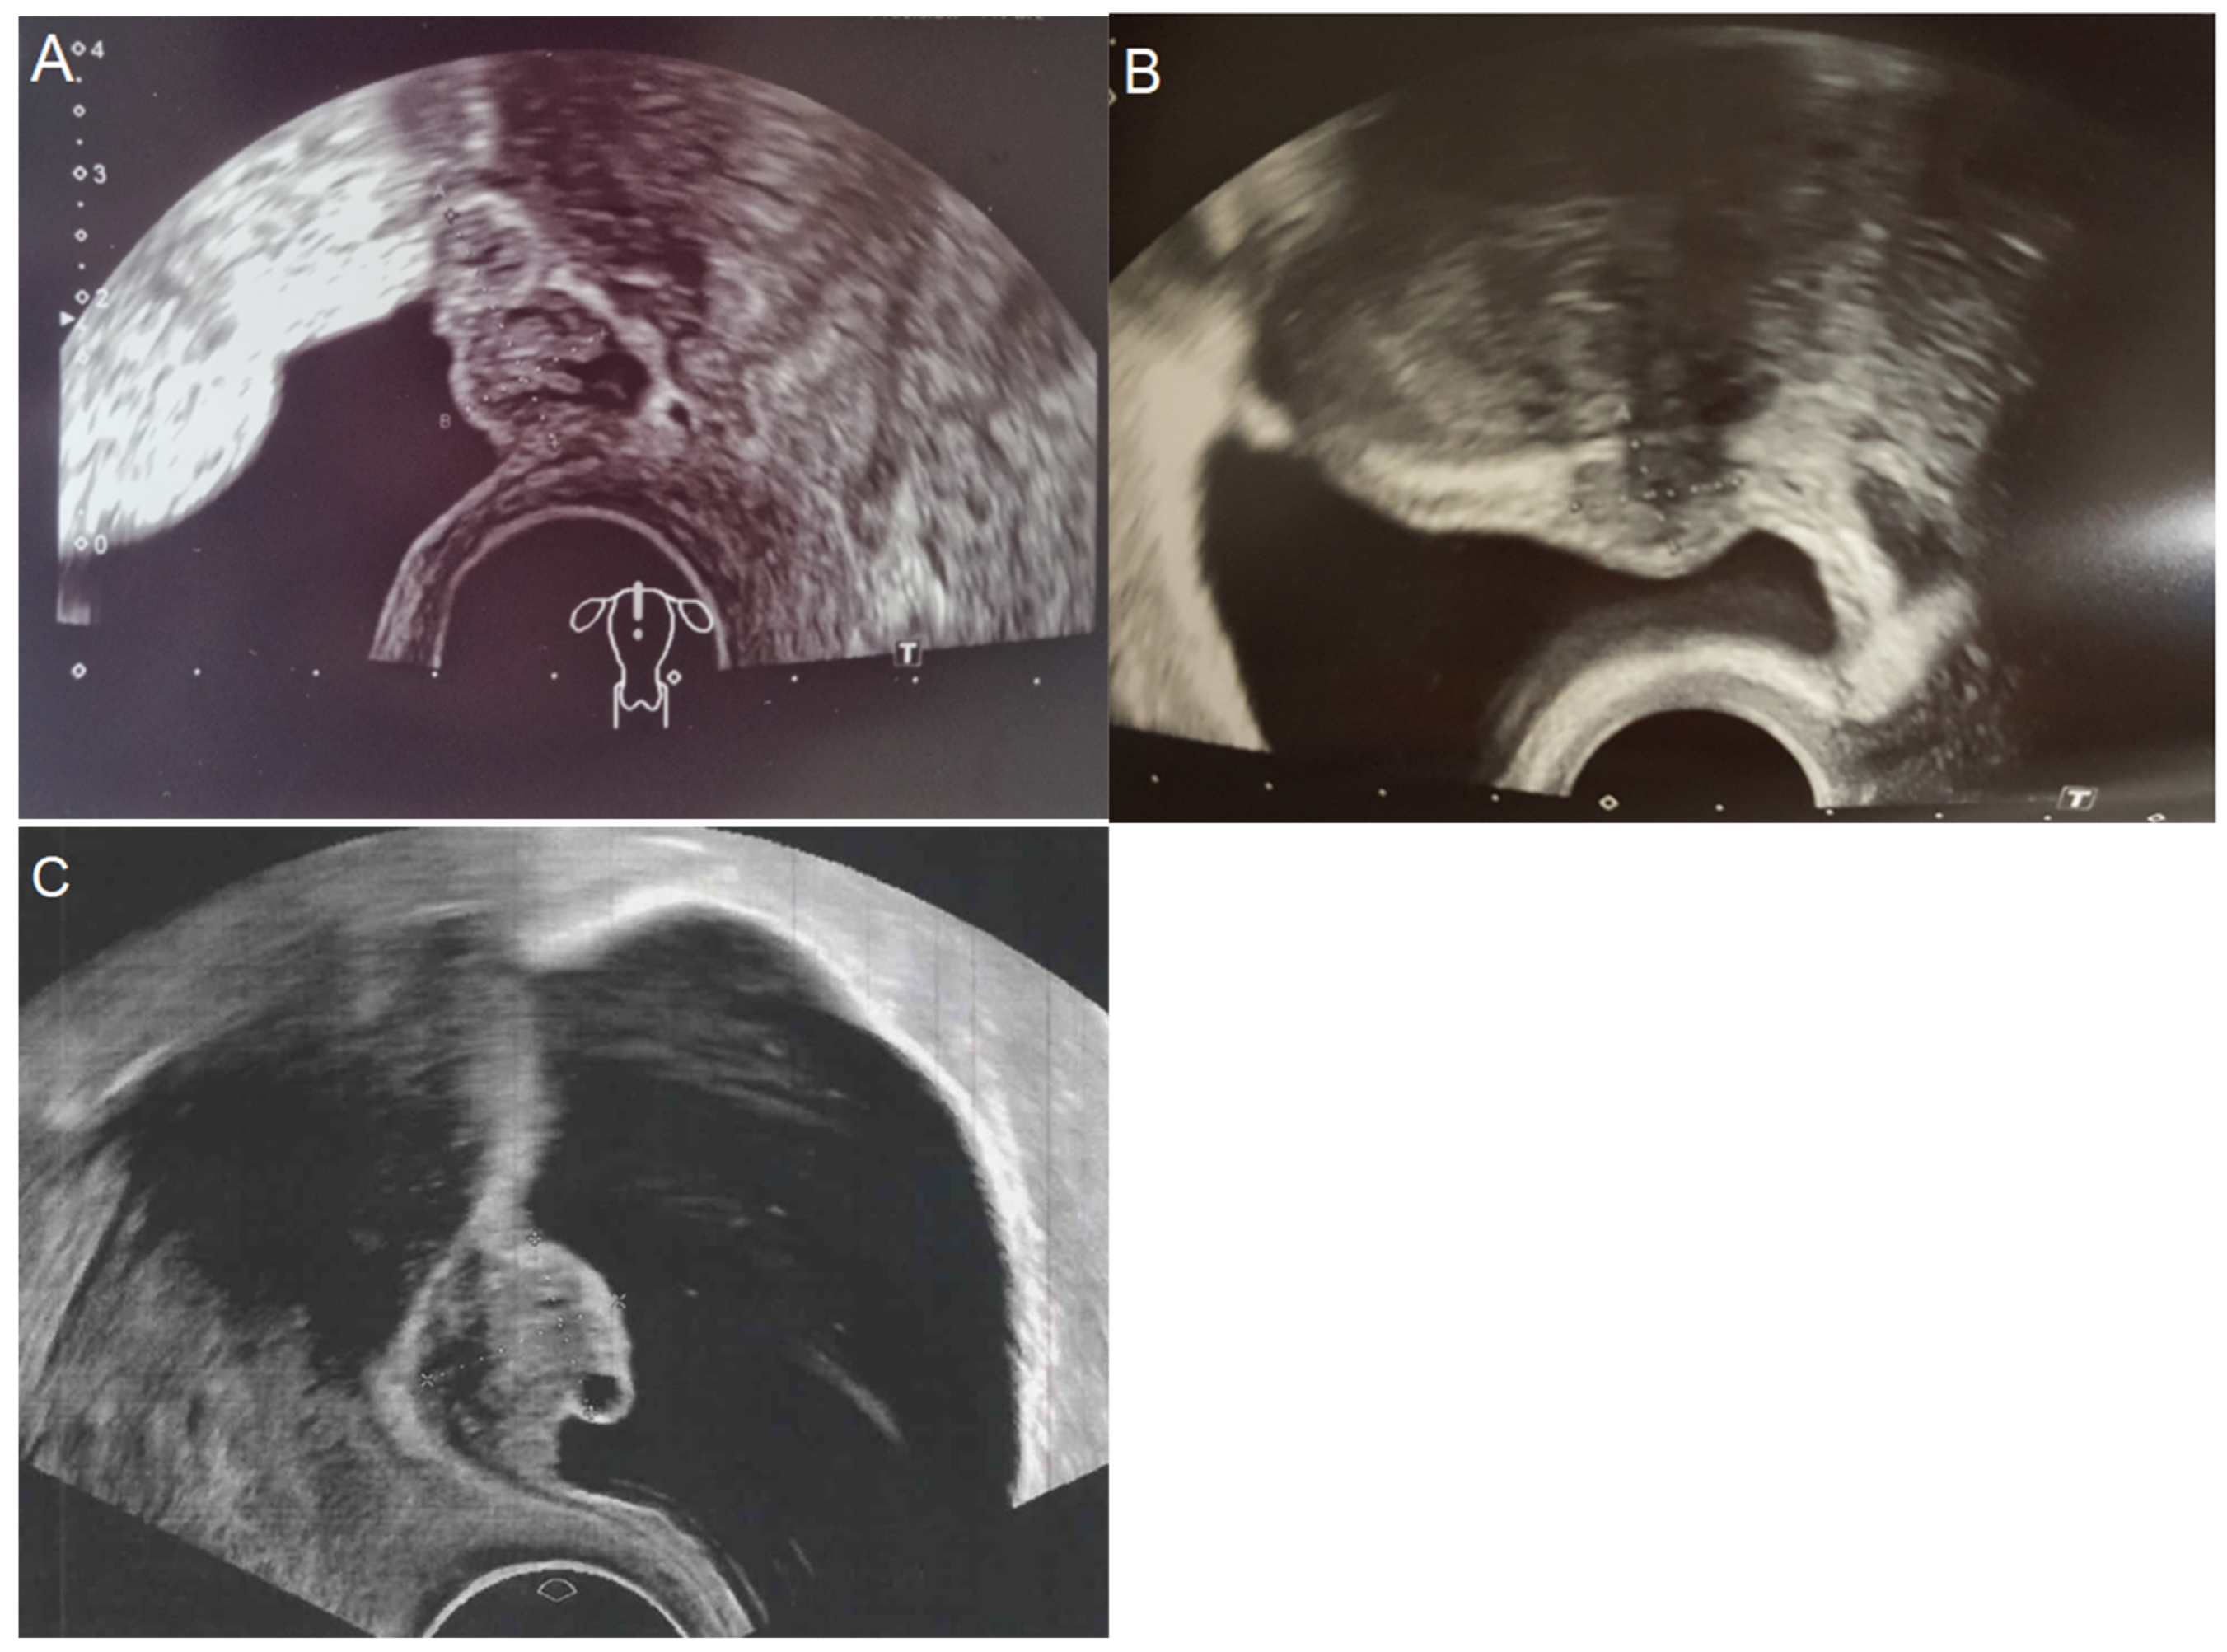

3.2. Preoperative Management